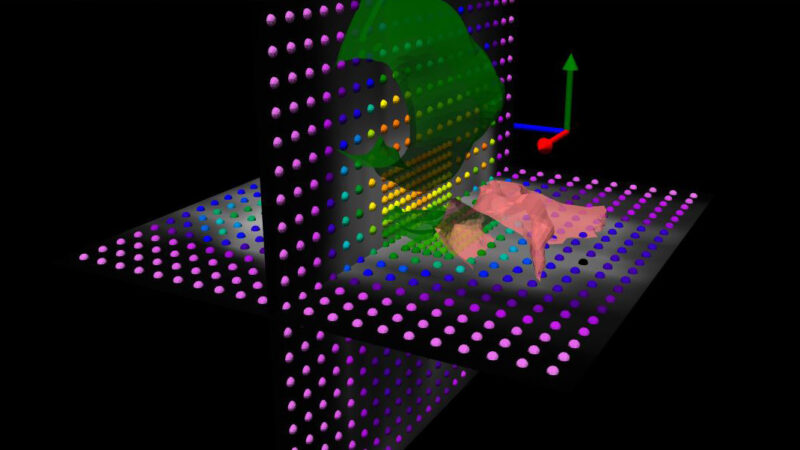

With the Delta4DVH Anatomy software option, you can verify and analyze the dose that has been delivered to the patient anatomy. Based on the measurements in the isocentric target region and dose calculation of the dose in the patient anatomy you now have a truly independent verification of the delivered dose.

With QA based on real measurements, there’s no need to trade accuracy for efficiency.